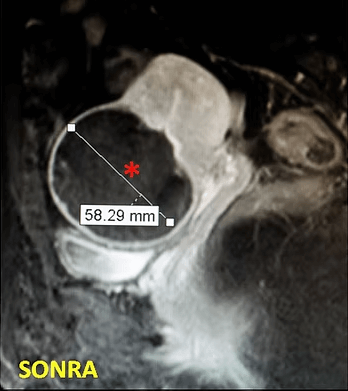

32 yaşında, kansızlık, gaz, sık idrara çıkma şikayetleri var. Emar’da 9 cm çaplı tek miyom (*) mevcut. Tek seans perkütan ablasyon sonrası miyomun belirgin küçüldüğü izleniyor. İşlemden 5 ay sonra hasta şikayetleri kalmamıştır.